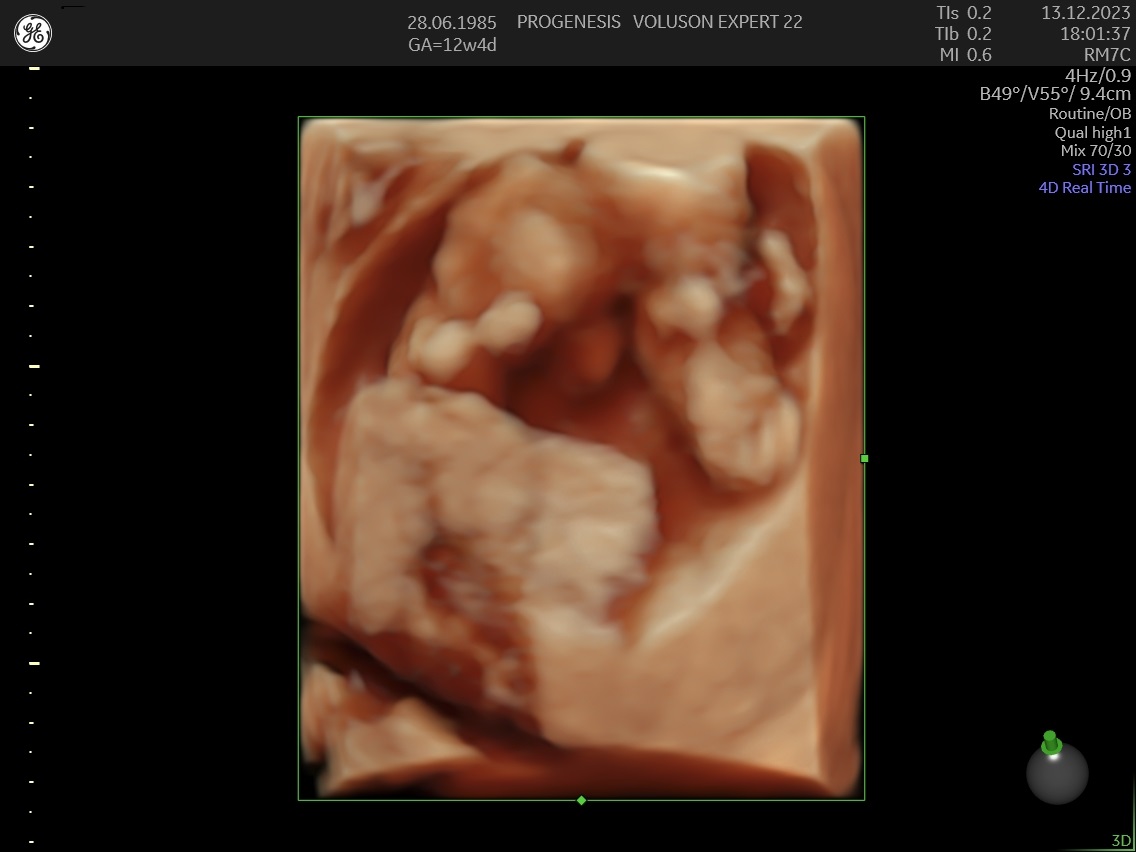

Το υπερηχογράφημα της αυχενικής διαφάνειας, πραγματοποιείται από τις 11 εβδομάδες +1 ημέρα έως 13 + 6 ημέρες κύησης και σε μήκος εμβρύου από 45mm έως 84mm.

Η εξέταση της αυχενικής διαφάνειας, ξεκίνησε με στόχο την ανίχνευση των εμβρύων με σύνδρομο Down, αλλά με την πάροδο των χρόνων, εξελίχθηκε στον πρώτο σημαντικό έλεγχο της ανατομίας του εμβρύου.

Διάγνωση ανατομικών ανωμαλιών

Πολλές και σημαντικές ανωμαλίες, όπως ανεγκεφαλία, απουσία άκρων, ομφαλοκήλη, ορισμένες συγγενείς καρδιοπάθειες και άλλες ανωμαλίες, είναι ορατές απ' αυτό το στάδιο της κύησης. Δίνουμε ιδιαίτερη έμφαση στην αξιολόγηση της καρδιάς των εμβρύων, τόσο για την αξιολόγηση χρωμοσωμικών ανωμαλιών όσο και πρώιμη ανίχνευση συγγενών καρδιοπαθειών από το 1ο κιόλας τρίμηνο (π.χ. υποπλασία καρδιάς, συγγενή μετάθεση μεγάλων αγγείων).